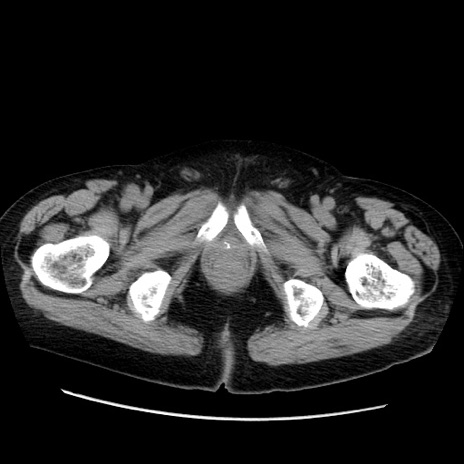

冠状断像

症例21(横断像)

【症例】70歳代男性

【主訴】腹痛

【現病歴】肝硬変・肝細胞癌にてかかりつけの方。約9時間前に食後より腹痛出現。症状が徐々に増悪し、嘔吐出現したため来院。

【既往歴】肝硬変、肝細胞癌(RFA、TACE後)

【身体所見】意識清明、表情苦悶様、BT 36℃、BP 129/78mmHg、P 88bpm、SpO2 97%(RA)、右上腹部から心窩部にかけて圧痛あり、反跳痛なし、筋性防御あり。

【データ】WBC 5800、CRP 0.16